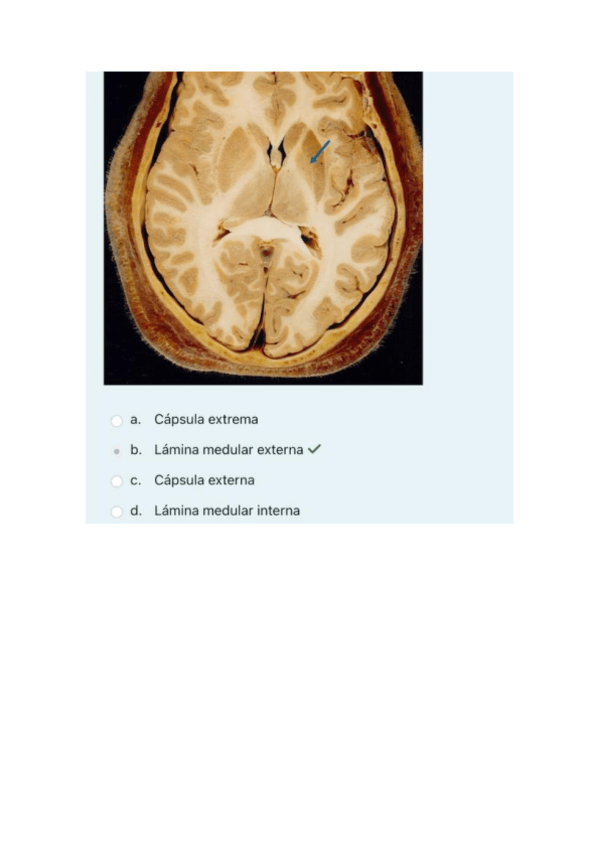

He publicado nuevos practicas de 4º neuroanatomía y anatomía de los órganos de los sentidos: todo-PRACTICAS-NEUROANATO.pdf

47 páginas

01.-Parcial-1-2023-teoria-resuelto.pdf

1o-parcial-practicas-2024-neuroanatomia-resuelto.pdf

1o-parcial-teoria-2024-neuro-resuelto.pdf

02.-Parcial-1-2023-practica-resuelto.pdf

2o-parcial-practicas-2024-neuroanatomia-resuelto.pdf

2o-parcial-teoria-2024-neuroanatomia-resuelto.pdf